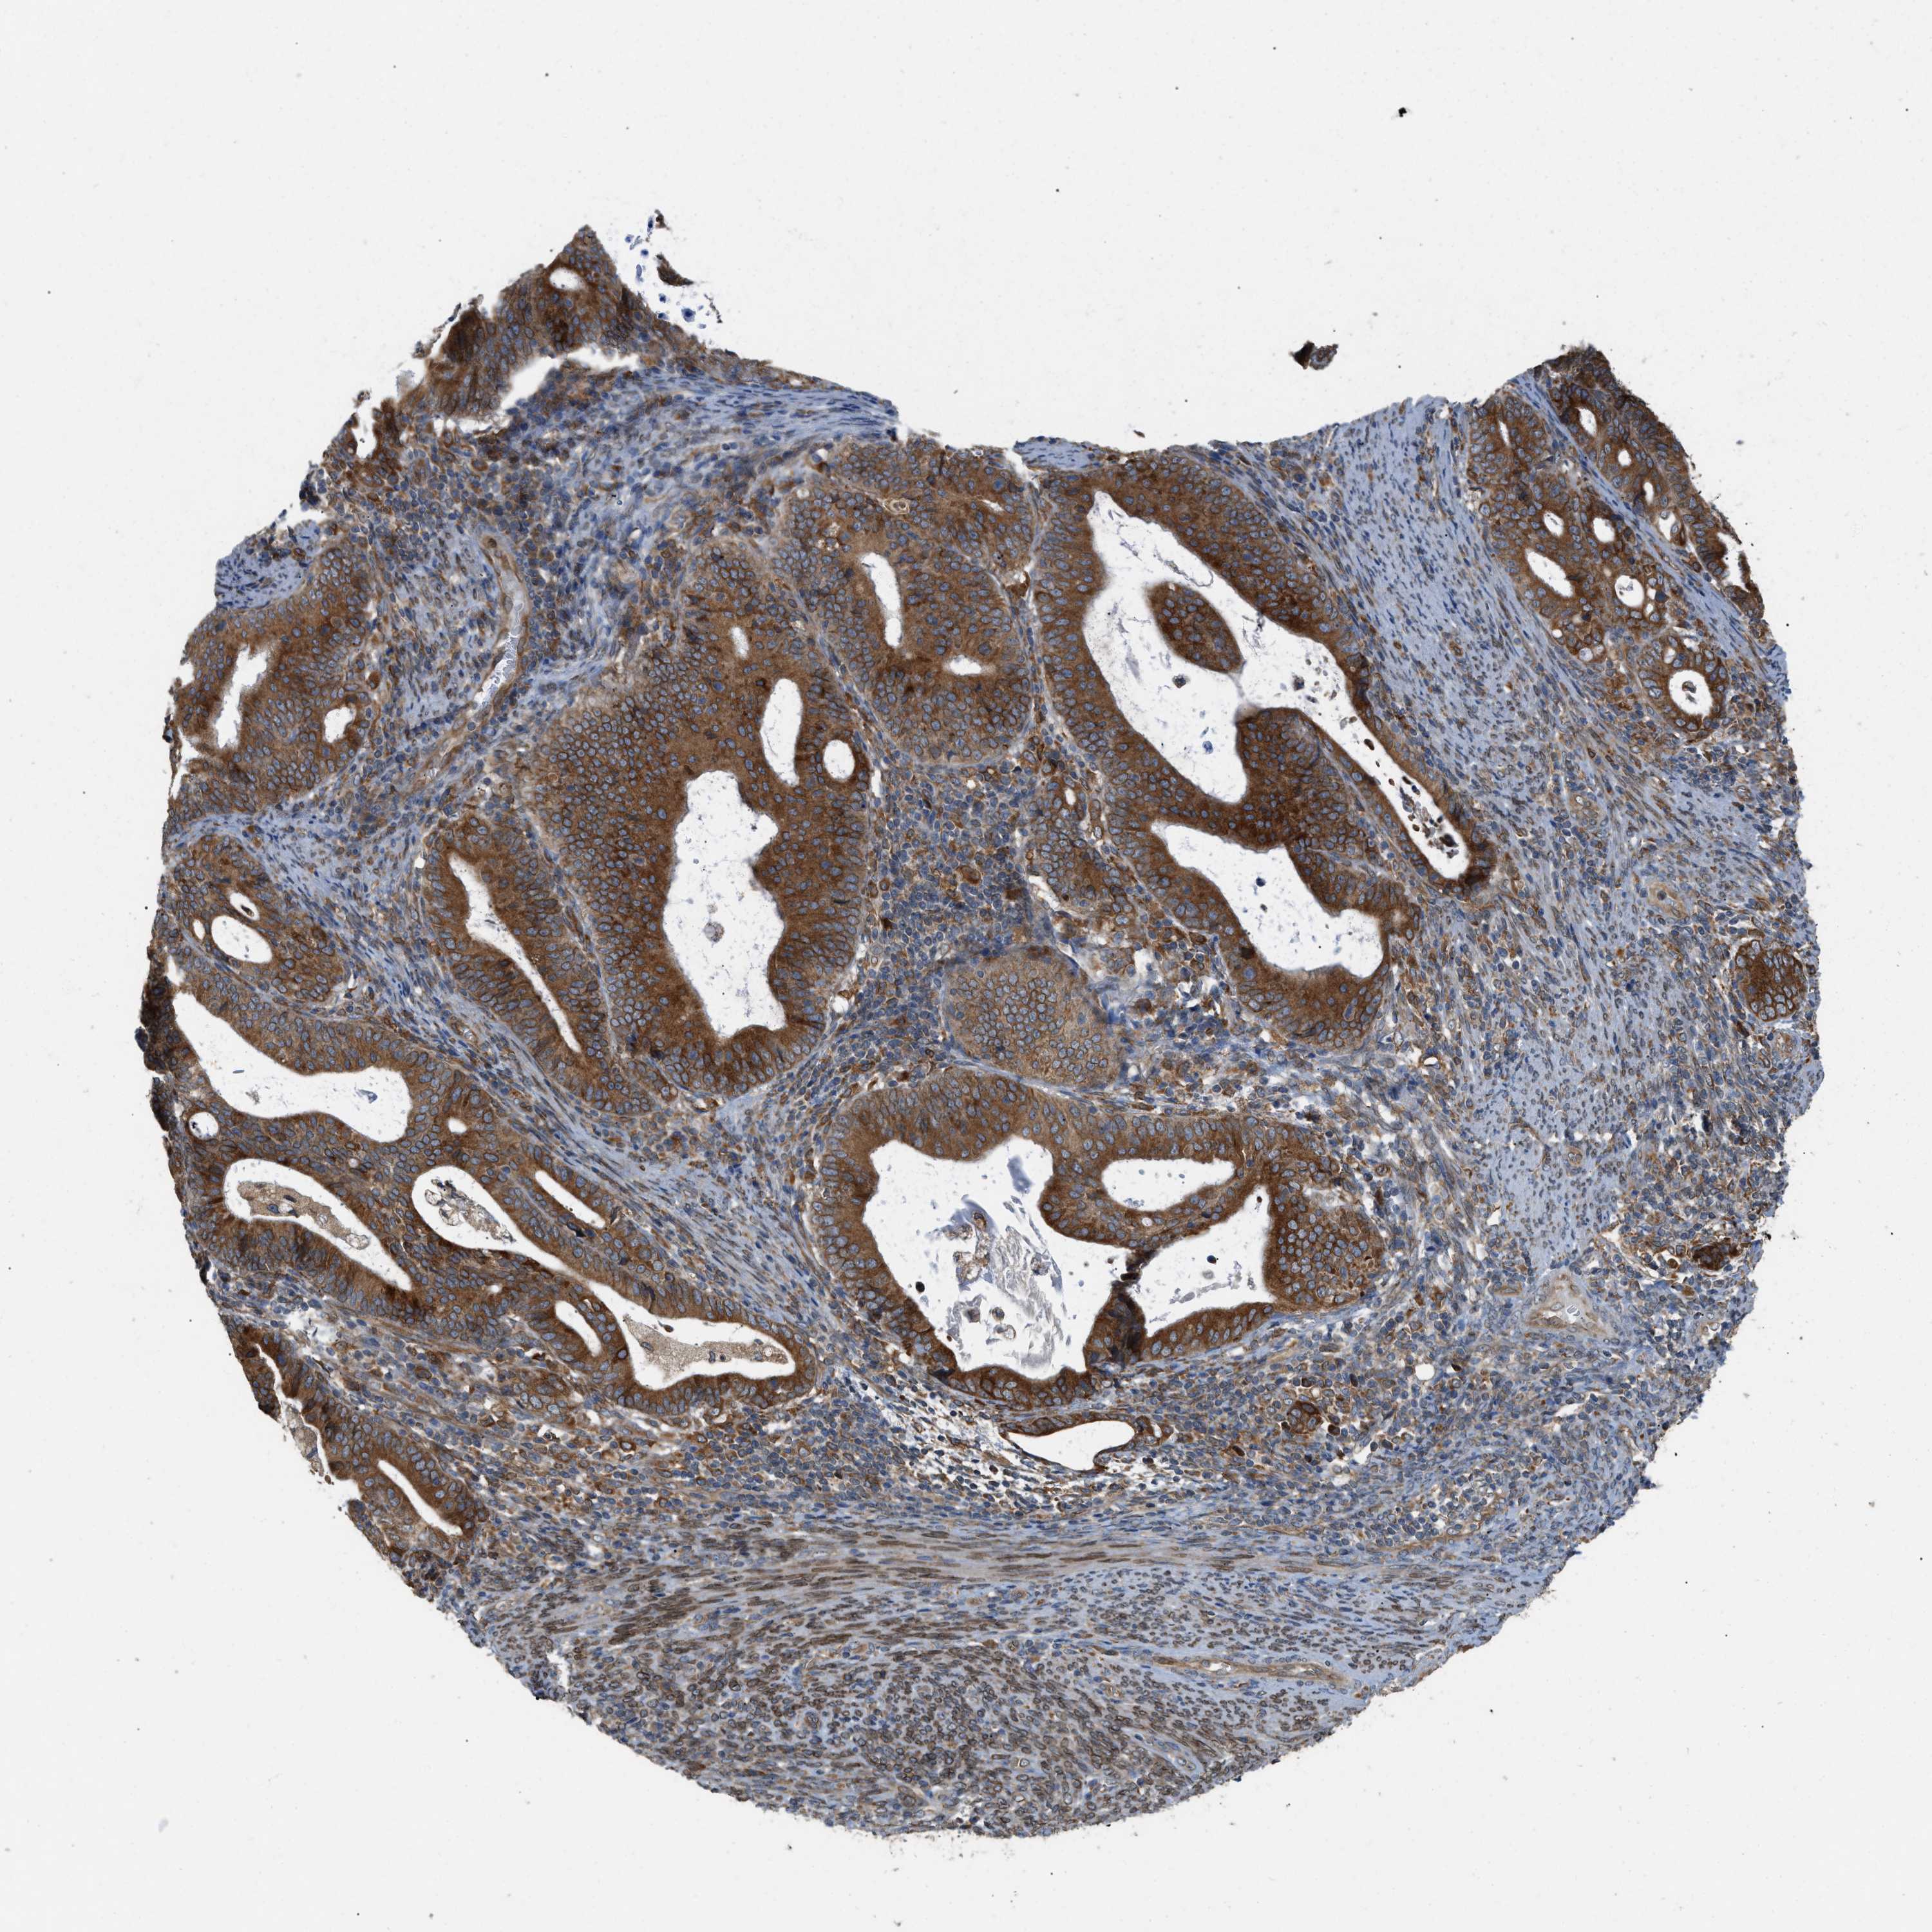

ENDOMETRIAL CANCER - Protein expressioni

A mouse-over function shows sample information and annotation data. Click on an image to view it in a full screen mode. Samples can be filtered based on level of antibody staining by selecting one or several of the following categories: high, medium, low and not detected. The assay and annotation is described here.

Note that samples used for immunohistochemistry by the Human Protein Atlas do not correspond to samples in the TCGA dataset.

Antibody stainingi

Antibody staining in the annotated cell types in the current human tissue is reported as not detected, low, medium, or high, based on conventional immunohistochemistry profiling in selected tissues. This score is based on the combination of the staining intensity and fraction of stained cells.

Each image is clickable and will lead to virtual microscopy that enables deeper exploration of all samples and also displays staining intensity scores, fraction scores and subcellular localization as well as patient and tissue information for each sample.

Antibody HPA014394

Staining

High

Medium

Low

Not detected

Intensity

Strong

Moderate

Weak

Negative

Quantity

>75%

75%-25%

<25%

None

Location

Nuclear

Cytoplasmic/membranous

Cytoplasmic/membranous,nuclear

Adenocarcinoma, NOS